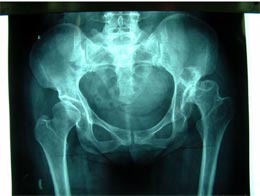

病例三

患者女性,45岁,左髋关节先天性脱位,股骨头坏死,疼痛明显,活动受限。采用生物固定全髋关节置换术,

髋臼予以加深没有植骨。术后5年复查,假体没有松动,关节功能良好,没有疼痛。